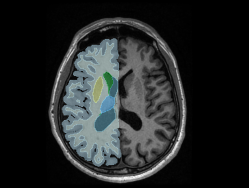

Literatürce kabul edilmiş en geçerli yöntemleri kullanarak, beyin atlasları ve derin öğrenme metotları ile beyin yapılarının 3D  modellenmesi

Beyin MR görüntülerinin segmentasyonu ve parselasyonu, analize hazır hale getirilmesi

Hipokampüs ve Amigdala 3D Modellenmesi